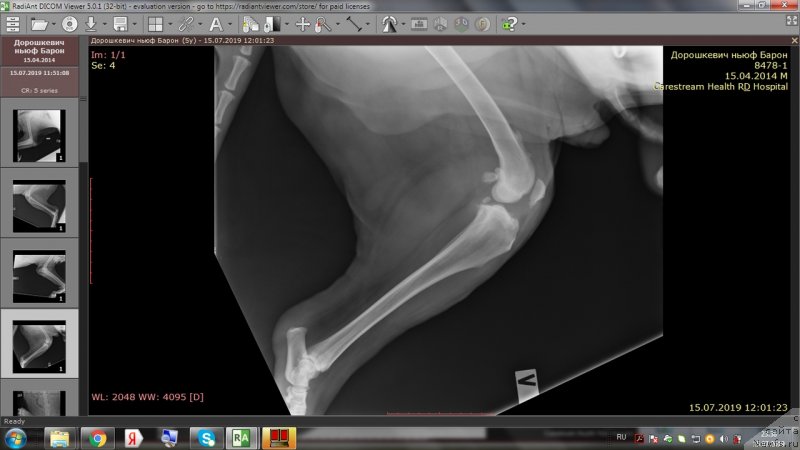

На приёме у врача.

Фотография № 243971

Quote:Вера 12:51

Сейчас у доктора

Бароша врачам всем нравится))))

Фотография № 243972

Фотография № 243973

Quote:Они его гладят,а он балдеет

Восхищаются характером

Подробности уже позже.

Доброе утро,уважаемые форумчане!Вот и проползли черепашкой эти томительные 2 недели до повторного приема врача.И,вновь,к нашей радости,не подтвердились самые худшие опасения😊.Барошенька похудел на 3 кг.На снимках,как видно,в более-менее живом состоянии только правое колено.Локти не сгибаются из-за махровых наростов,с левым коленом ситуация хуже остальных лап,на прогулке,после лежания,первые несколько метров в колене слышно перестукивание суставов,но потом все проходит.Лечение идёт на пользу,колени стали лучше сгибаться,огромный отёк с левого колена спал,и писает теперь не приседая полностью до земли и не плюхаясь пузом от усталости в свою лужу.На прошлой неделе созванивались с доктором и немного подредактировали терапию-отменили тобрекс,т.к.не было результата и заменили на офтагель,флоксал,в связи с тем ,что у Бароши синдром сухого глаза и заворот века(рекомендовано в будущем провести операцию).Сегодня обновлю запасы этих лекарств.Антибиотик доксифин продлили до 8 недель,но купила пока на 2 недели,т.к.финансов не хватит на такой курс.Полное,качественное восстановление займет месяца 2.Сейчас то тут,то там выскочит экзема,соскоб с экзем показал наличие грибов-коки,эзофилы.Тут и стресс перенесенный и смена климата и т.д.